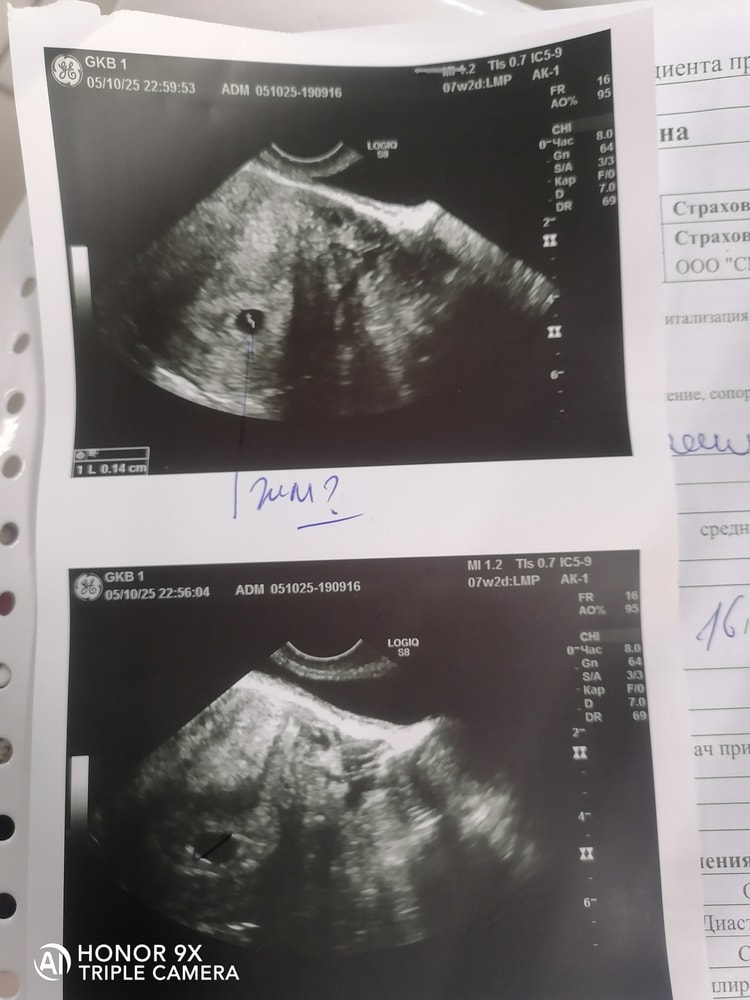

Пару дней назад писала, что на узи показало ПЯ 12мм, нет ЖМ и эмбриона. Срок от месячных 7 недель, на узи 5 недель поставили. Хотела завтра пойти на узи с утра к др специалисту, но теперь не знаю как быть. Сейчас начало кровить. Ноет низ живота как на М. Я понимаю, что скорее всего это организм отторгает ПЯ. Вызвать скорую не могу, тк одна с сыном, ему 5 лет и если меня сейчас увезут в стационар, то его не с кем оставить, муж в командировке.

Елена, съездила в больницу. Ставят Анембриония под? Дали неделю ещё. Узи сделали-толи есть ЖМ, толи нет. Назначили дюфастон